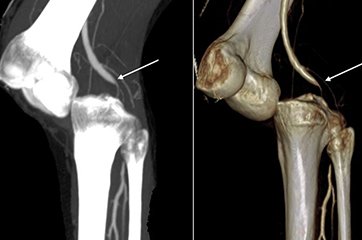

With their state-of-the-art office in the Health City, Arilova, Visakhapatnam, the “Vizag Vascular Center” is an innovative Hospital for comprehensive Vascular care with a world-renowned team of qualified Vascular and Endovascular surgeons, who are recognized as the best in the treatment of Vascular diseases. The team includes highly trained surgeons and physicians dedicated exclusively to the care of disorders of the circulatory system, including the arteries and veins. They help patients optimally manage vascular conditions, whether through diet, exercise and medication, open surgical or minimally invasive interventional procedures.